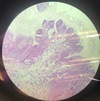

Lymph node, inverted.

(Lymphonodus inversus)